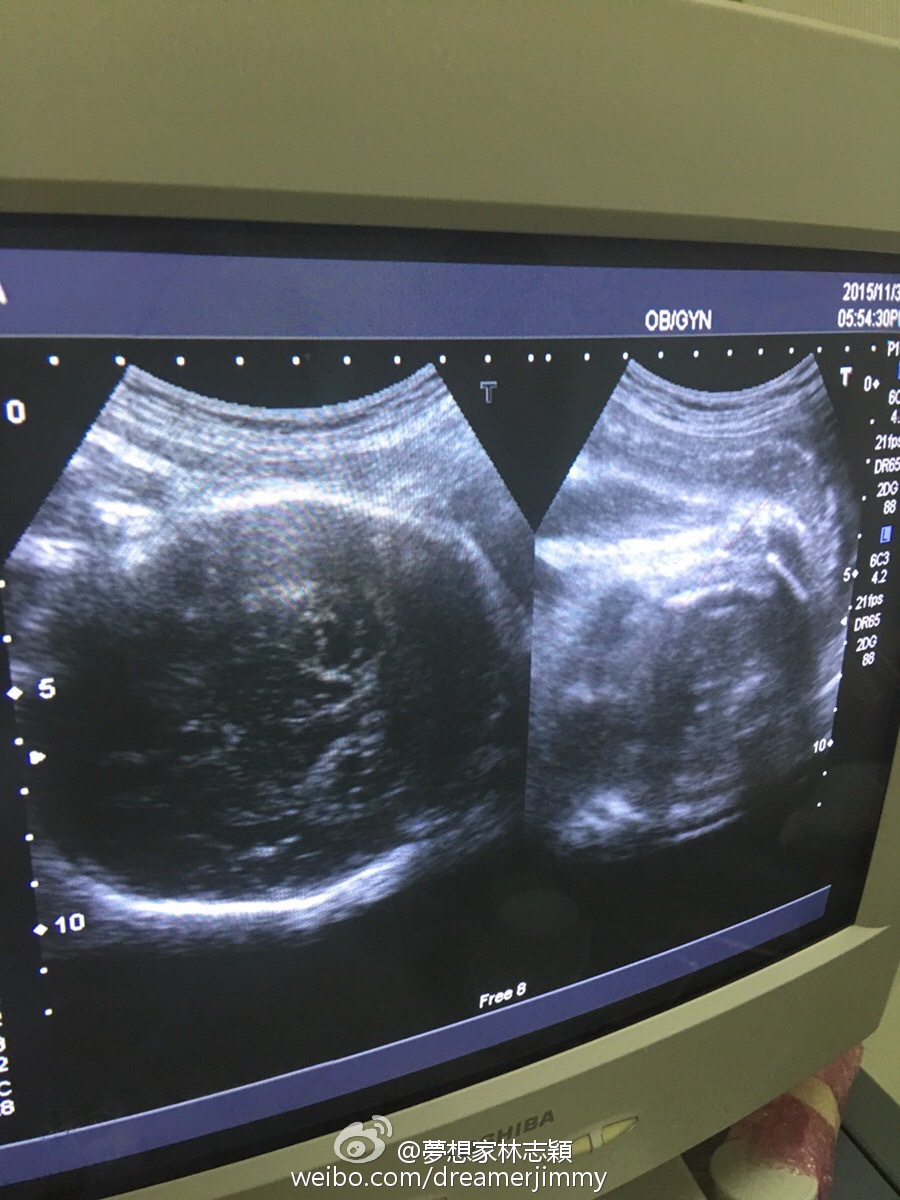

【now.com】台灣「童顏不老」男星林志穎再做老竇!台灣傳媒報道,老婆陳若儀今朝10時在台北剖腹產下雙胞胎囝囝,下午4時左右林志穎就立即放相上微博同大家分享喜悅。

已經育有五歲大兒子Kimi的林志穎,再添一對孖仔,家庭成員增至5人。據報道,一對孖仔相當健康,哥哥重5.82磅,弟弟就重5.81磅,兩兄弟外貌不同,屬異卵雙胞胎。林志穎又在微博興奮地說:「在大家的祝福下,兩位小王子順利誕生了,謝謝大家」又晒出抱著孖仔的合照,Fans都紛紛留言恭喜。林志穎又話已經改了孖仔英文名,哥哥會叫Jenson、弟弟叫Kyson,名字都以林志穎和太太英文名(Jimmy及Kelly)的字頭取名。